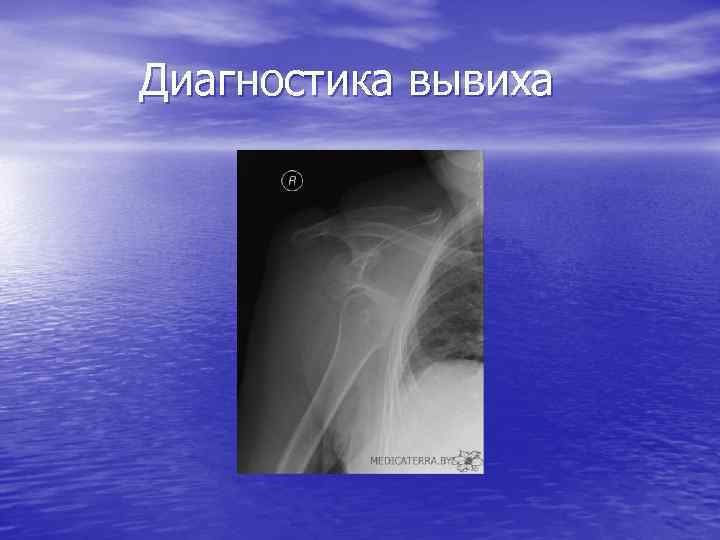

диагностика

диагностика

Диагностика вывиха

Диагностика вывиха